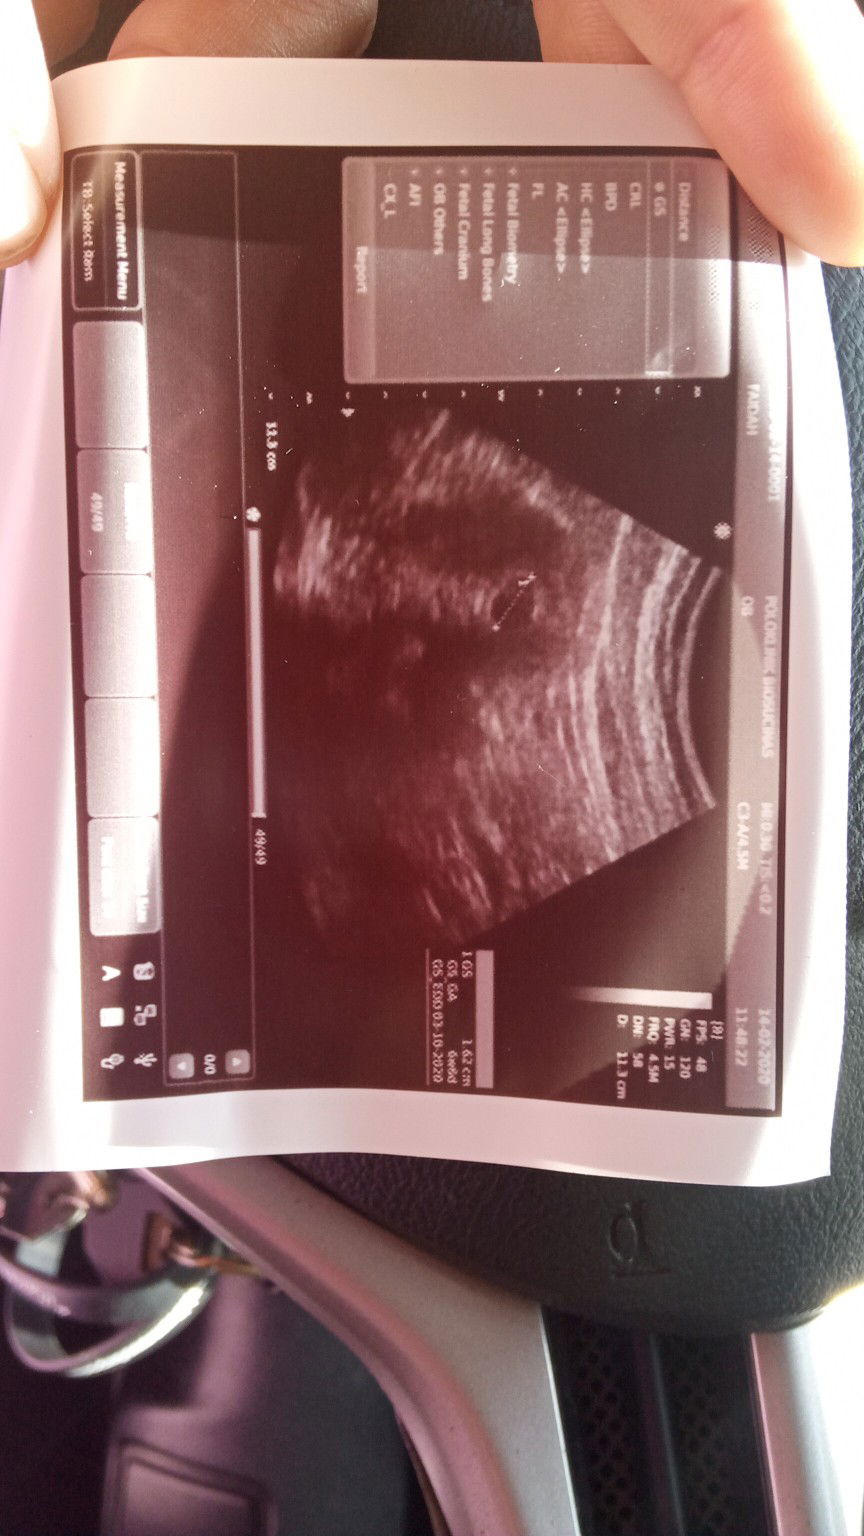

2 minggu yang lepas saya jalani ultrasound scan untuk tahu tentang janin saya. Doktor ada beritahu kandungan saya 6 minggu dan ikut kiraan tarikh awal period saya sepatutnya 8 minggu. Harini saya lakukan ultrasound sekali lagi. Dan dapati kantung tidak membesar mengikut sepatutnya. Tarikh due date yang diberi sebelum ini 23/9/2020 tapi harini jadi 3/10/2020. Apa patut saya lakukan. Doktor menasihatkan untuk jalani ultrasound 2 minggu sekali